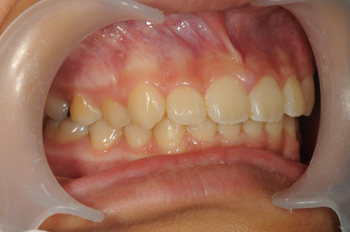

Before

小さい頃から通って頂いている患者様です。大きくなるに連れ、前歯の歯並びが特に気になりだしたということで、ご両親ともカウンセリングにお越しいただき、現状と今後についてしっかりお話させて頂いた結果、矯正治療をスタートすることになりました。